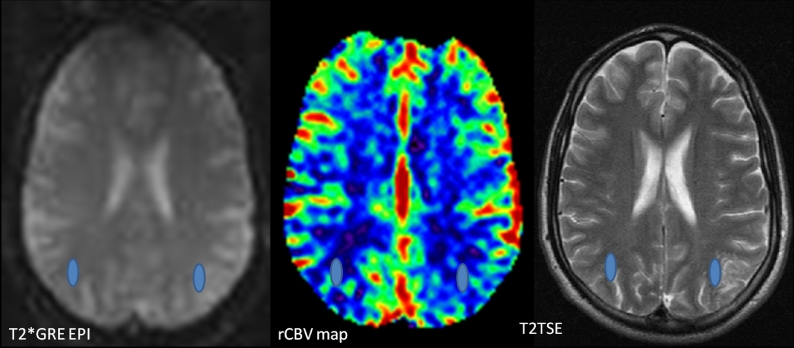

Fig. 2.

For the T2* DSC-perfusion MRI a 2D single-shot multislice Gradient Echo Echo Planar Imaging (GREEPI) sequence was used. Relative CBV values of the lesion and the contralateral white matter were estimated by using the T2TSE images for coregistration with the GRE-EPI images. The ROIs were placed at the bolus peak of the GRE-EPI images, to avoid vascular structures, and automatically transferred to the CBV map, using dedicated software (NordicIce, NordicNeuroLab, Bergen, Norway).